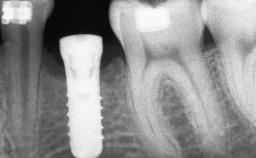

Guided Bone Regeneration (GBR) with a Particulated Autologous Graft and a ePTFE-Reinforced Membrane for Vertical Augmentation of a Single-Tooth Edentulous Space in the Esthetic Zone

# of Teeth 1

# of Implants 1

Type of Implants Two-Piece

Bone Augmentation Staged|Vertical